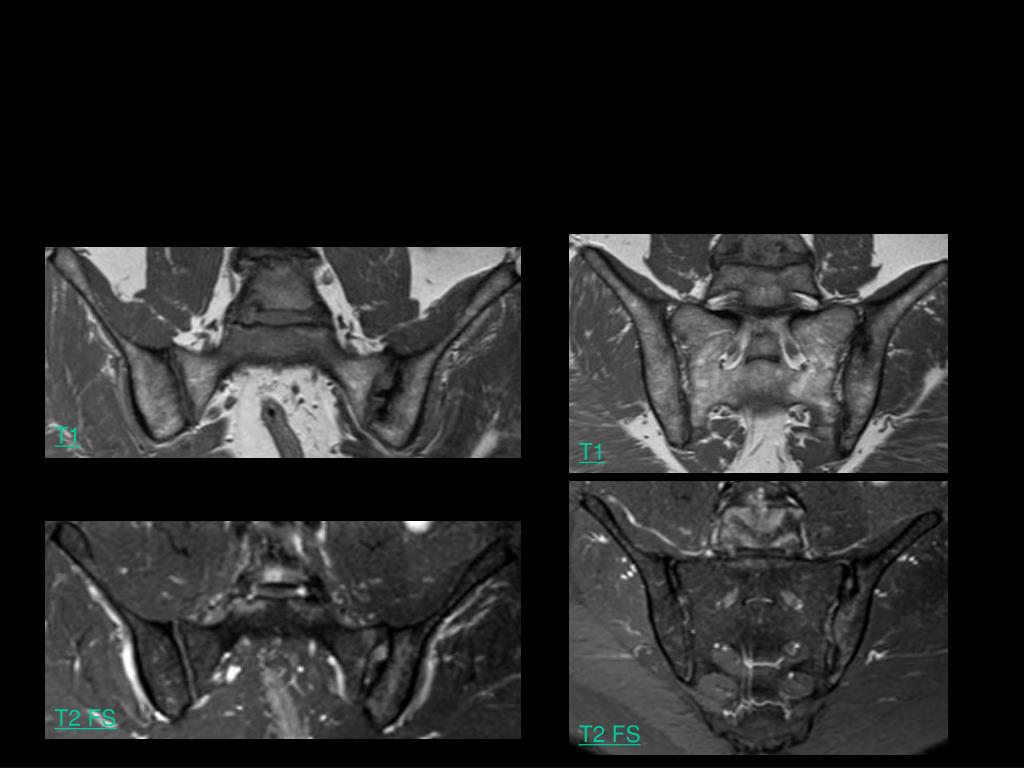

7. Ca se complique vraiment… Homme, 49 ans, rachialgies inflammatoires: spondylodiscite dans le cadre d’une SPA T1 T1 T2 FS T2 FS